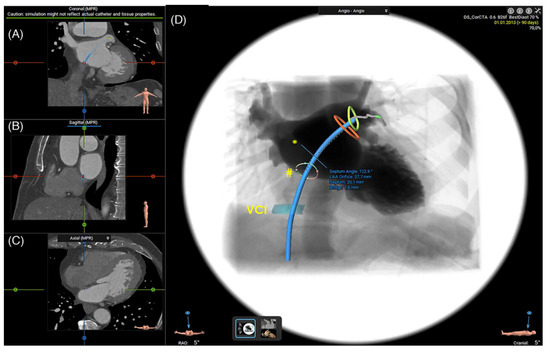

2.1.3. Assessment of the Inter-Atrial Septum

2.1.4. Other Anatomical Considerations